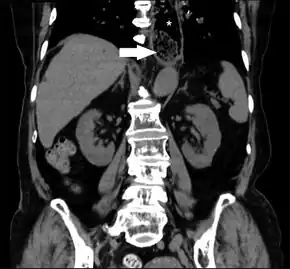

![]() | |

| Endoscopic image of patient with esophageal food bolus obstruction due to a grape in the setting of eosinophilic esophagitis | |